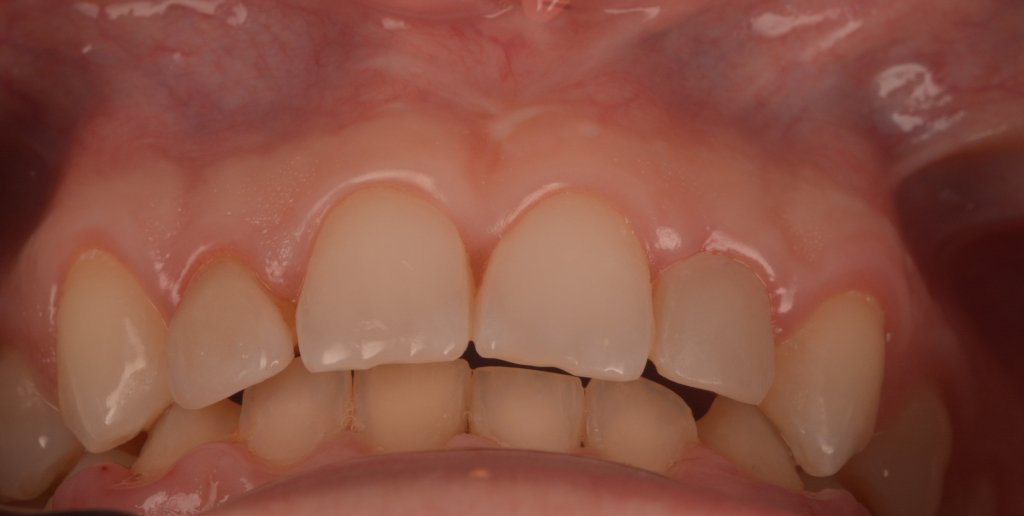

El momento más «bonito» para ti, para la paciente, para la auxiliar (Karla), y para Nacho…a ver si no rompemos sus MARAVILLAS (pero la culpa es siempre mía, que tallo cada vez menos)

(

Keep calm trás la retirada del Dique, esta encía volverá a su sitio (si habéis hecho bien la cirugía por supuesto).

2 SEMANAS DESPUÉS

No me asusta esta ligera inflamación, al revés se que están pasando cosas buenas, la encía se esta estabilizando y engordando según los principios de la técnica BOPT. Así que tengo tiempo para disfrutar simplemente del trabajazo de Nacho.